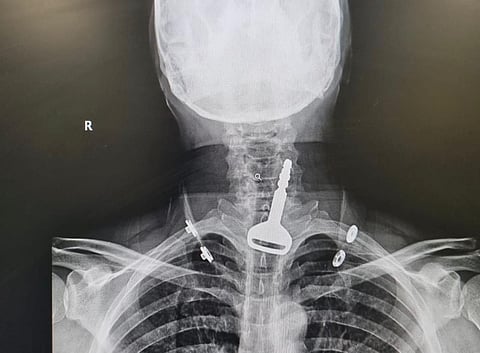

وأكدت "الصحة" في القنفذة أن الفرق الطبية تمكنت ولله الحمد من إنقاذ حياة مريض بعمر 49 عامًا أحضر لقسم الطوارئ يعاني من انسداد بمجرى التنفس، حيث اتضح بعد إجراء الفحص السريري والإشعاعي وجود مفتاح سيارة بمجرى التنفس.

وقال الفريق الطبي المشرف على الحالة: إن المريض كان يلهو بالمفتاح حسب ما توضح خلال الكشف، حيث تقرر فورًا إدخال المريض قسم العمليات وتكثيف العناية الصحية له؛ لكونه مريض قلب، وتم إجراء التدخل الجراحي عن طريق المنظار واستخراج المفتاح، ومن ثم متابعة الحالة عن طريق قسم التنويم لحين استقرار حالته الصحية وخروجه بالسلامة.